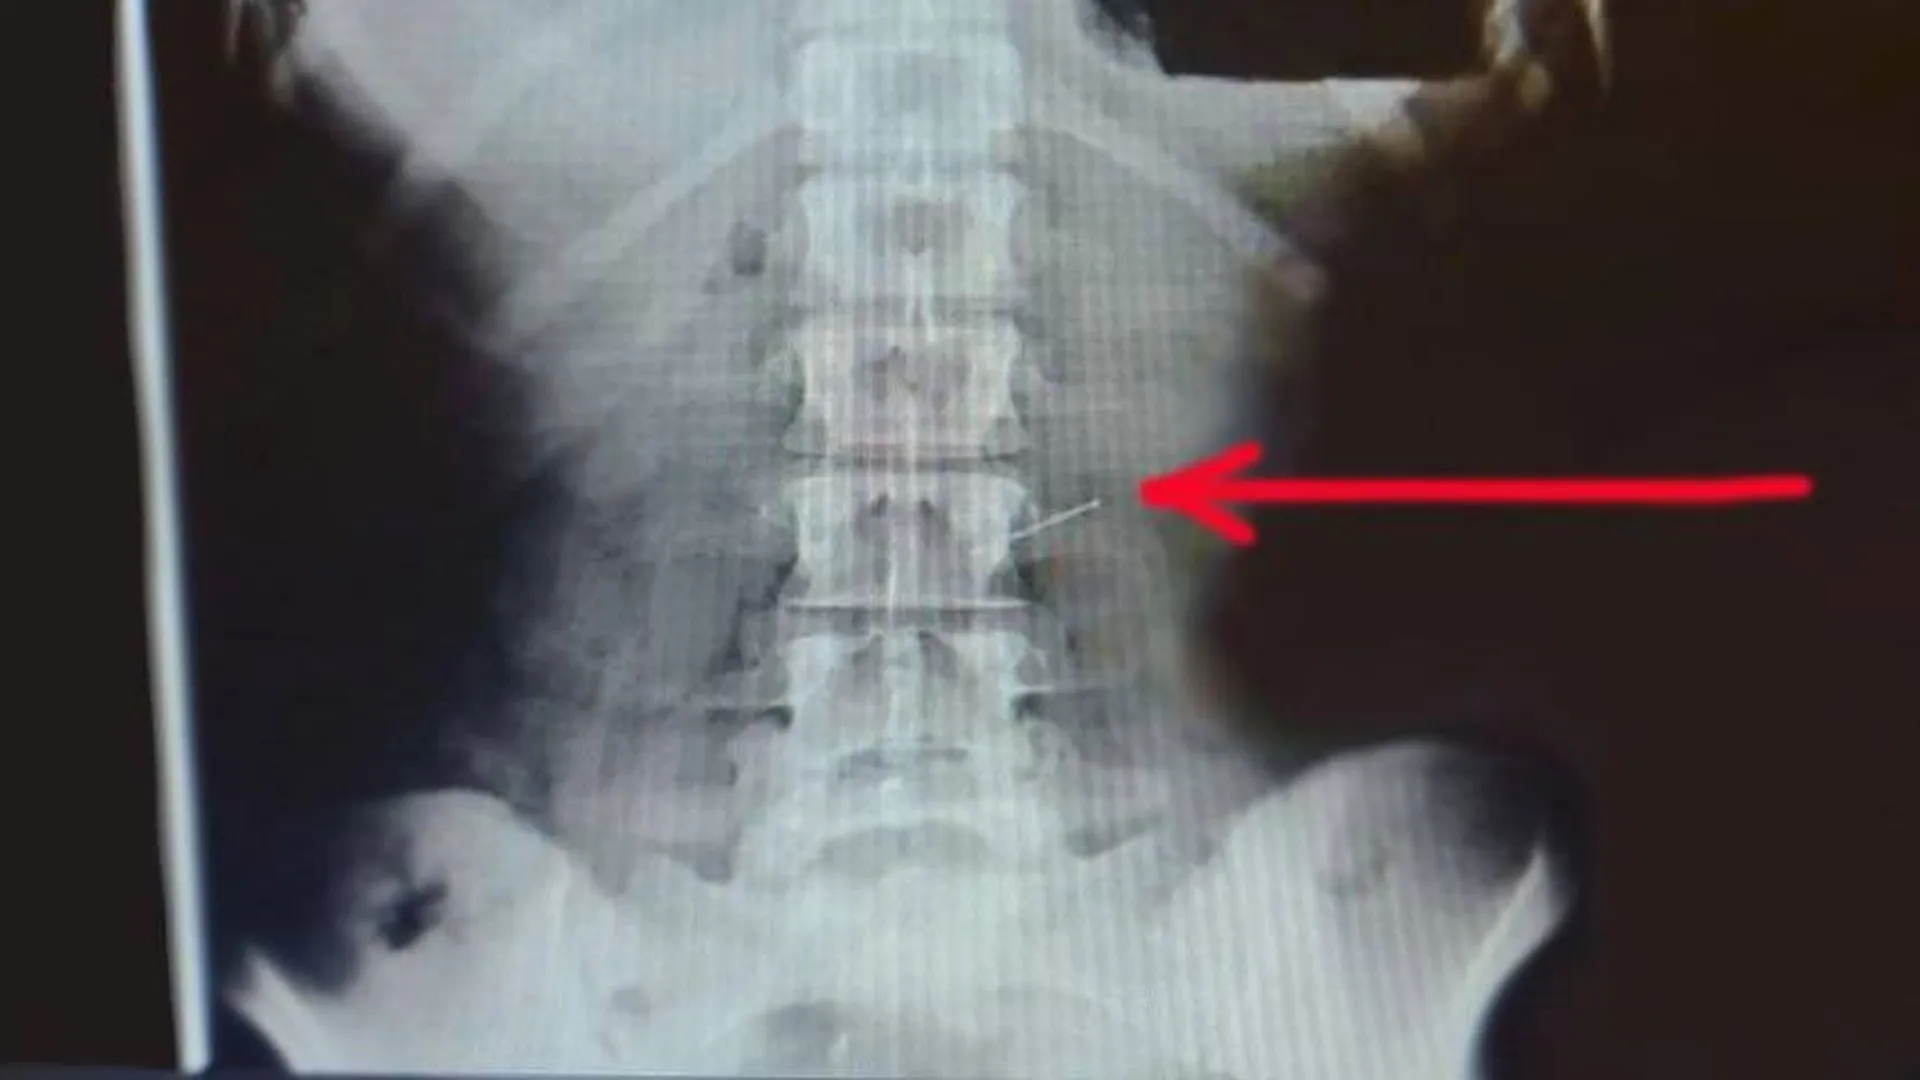

проглотил стекло

Что будет если случайно проглотил стекло 107 фотографий